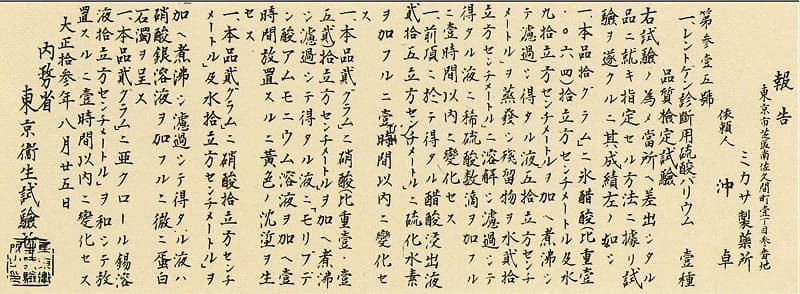

1924年

レントゲン診断用硫酸バリウム品質検査試験報告:内務省 東京衛生試験所

ミカバリウム試験報告書(販売許可証)